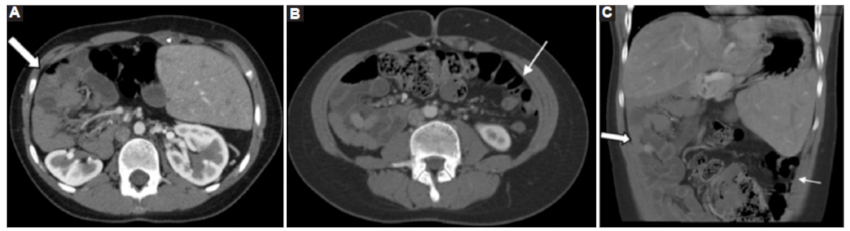

Hígado

En el síndrome de heterotaxia, la disposición central del hígado «en puente» es habitual junto con la vesícula biliar cercana a la línea media (casos 1, 2 y 3) (Fig. 12). En los casos 1 y 3 se observó remodelación hepática con hipertrofia del lóbulo izquierdo y del lóbulo caudado, determinando en el caso 3 una gran hepatomegalia (Fig. 12). Los casos 2 y 3 presentaron la vesícula biliar cercana a la línea media.